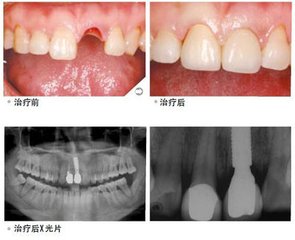

种植牙同烤瓷牙隶属于固定修复一类,之所以将其单独来讲,主要在于其拥有自己独立的牙根,修复以及使用过程无需影响到其他健康的邻牙。而且不管是牙齿稳固性还是牙齿咀嚼性都因为有了牙根,而变得稳固起来,带给我们品质生活感受。